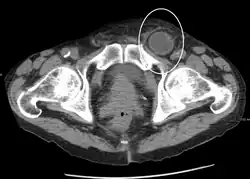

An incarcerated inguinal hernia as seen on cross sectional CT scan

A frontal view of an incarcerated inguinal hernia (on the patient's left side) with dilated loops of bowel above.

An inguinal hernia which contains part of the bladder. Bladder cancer is also present.